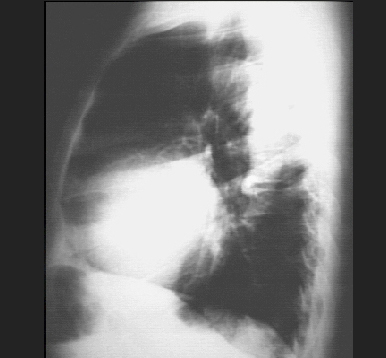

These chest X rays show left ventricular enlargement and a dilated aorta The PA view demonstrates cardiomegaly, as evidenced by a cardiothoracic ratio greater than 50%. Note also the increased inferolateral cardiac border that is consistent with ventricular enlargement due to volume overload. The ascending, transverse, and descending aortic shadows are also prominent. The lateral view shows left ventricular enlargement, as evidenced by posterior displacement of the left ventricular shadow.